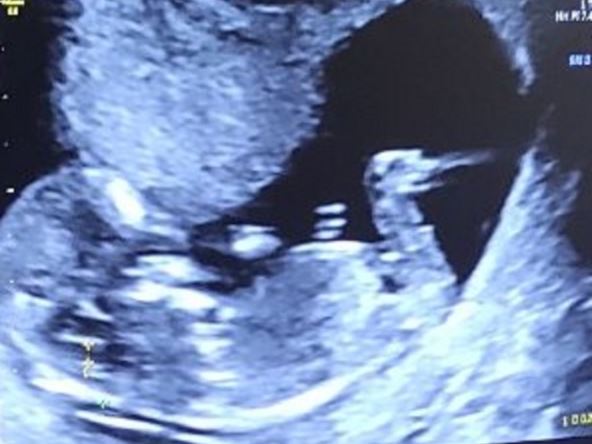

"Pozdrav za sve antivaksere i neuke kolege. Ova moja snajka je slušala skafandera, a ne vas, i devet nedelja nakon revakcine Fajzerom je dočekala da joj kažemo 'bićeš MAMA'! A pre toga četiri neuspešne VTO. Evo nova kontrola i trudnoća napreduje", poručila je.

Iako su mnogi u komentarima pisali da je glupo izjaviti da je vakcina zaslužna za trudnoću i da je Fajzer uspeo što nije vantelesna oplodnja, jasno je da namera ovog tvita nije bila ta, već da se pokaže ljudima da cepiva ne utiču na plodnost.